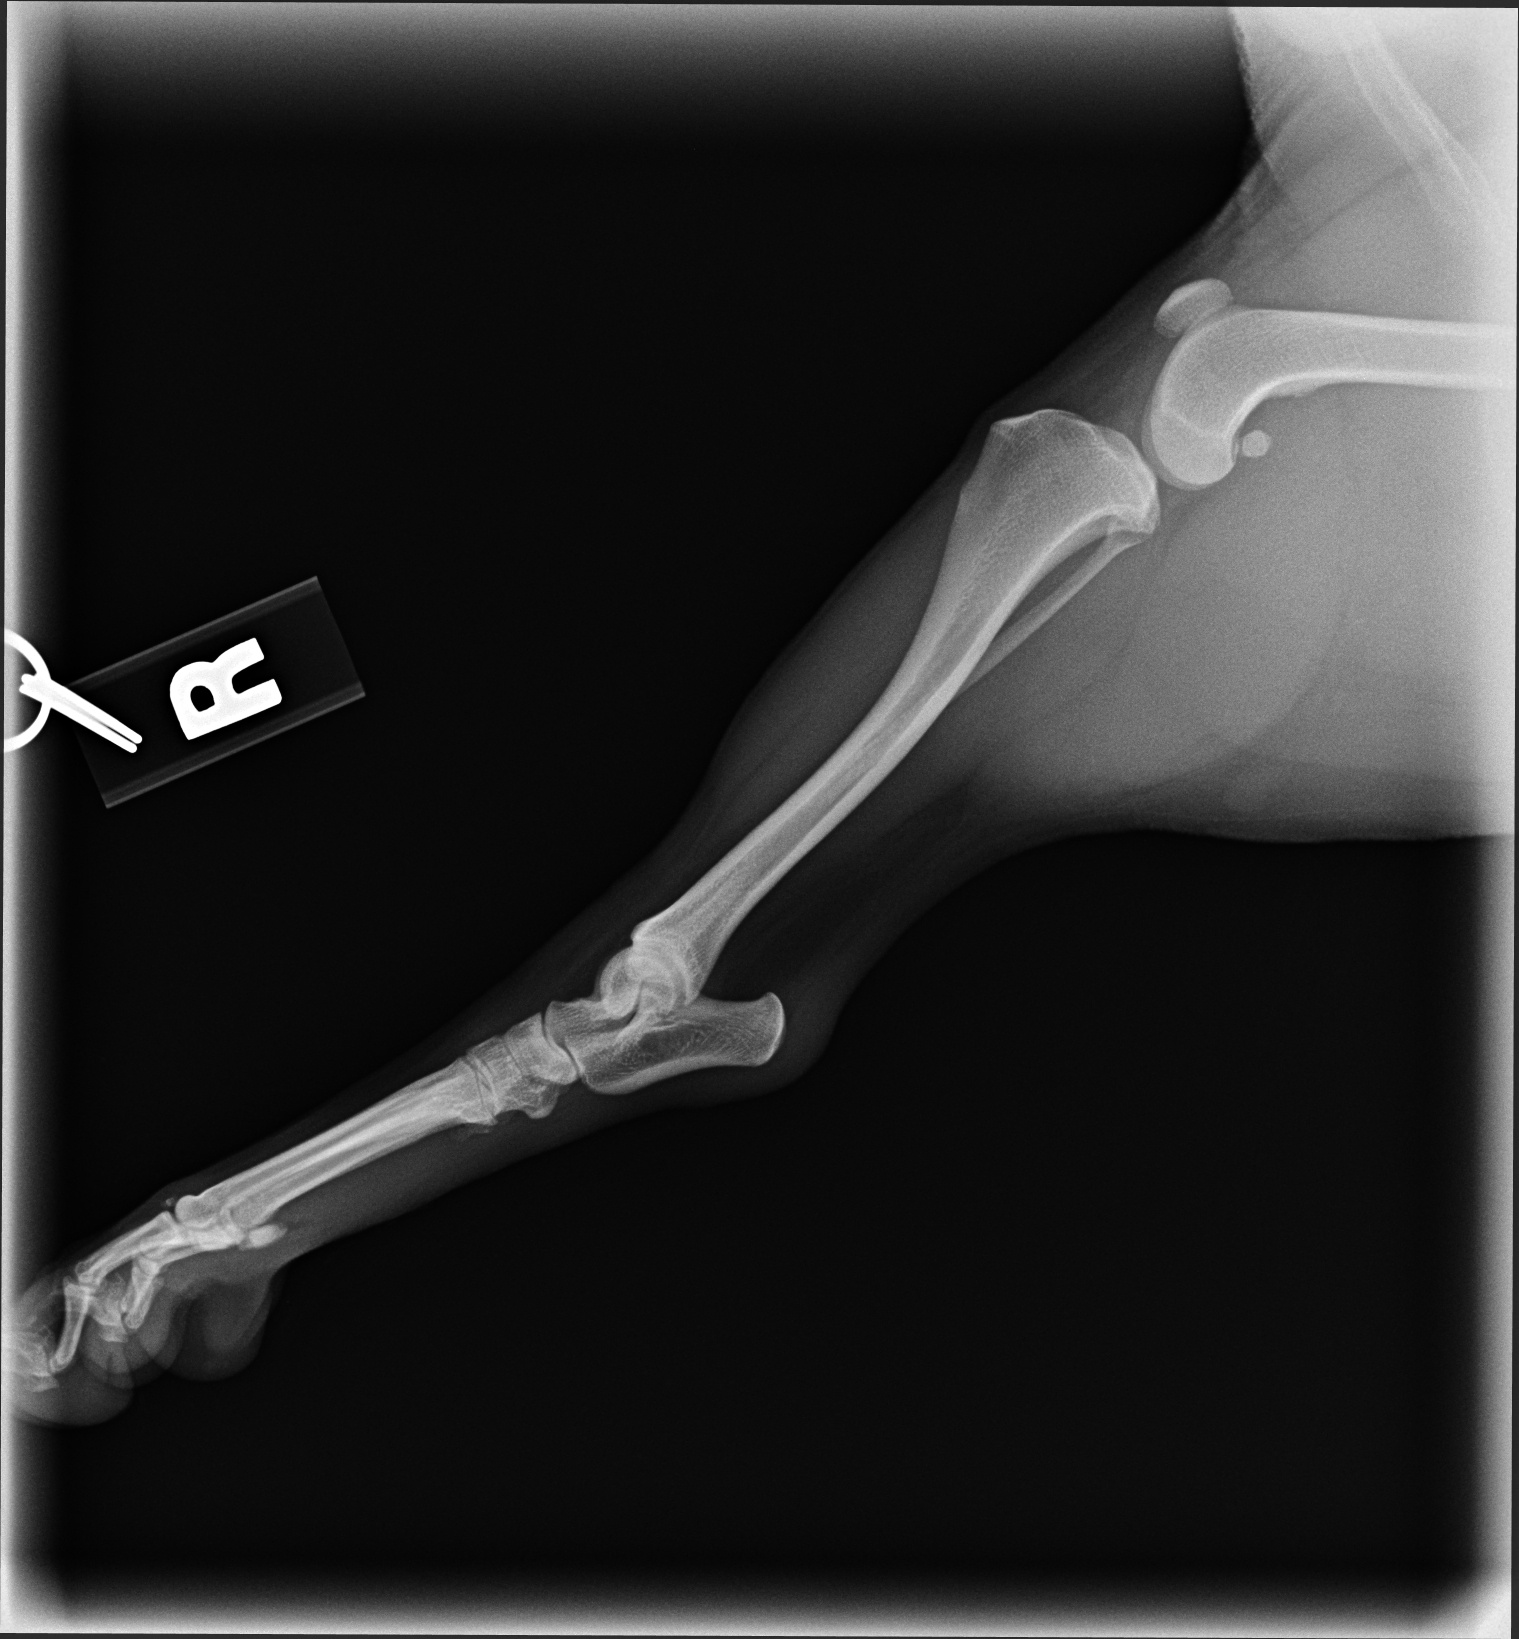

The images from the source dataset had issues and needed to be consolidated into a more usable framework. These issues were mostly due to inconsistencies in practices of radiographers and movement by the animals during radiography that resulted in radiographs with incomplete data, inconsistent image quality, such as varying contrast, brightness and positioning of point of interest or images that failed to meet the prerequisite conditions for this task. Examples of difficult data are shown in Fig. 5.

Most of the source dataset of over a thousand unique knee radiographs were distorted, had poor patient positioning, or were otherwise unfit for annotating. 250 of the original images were of sufficient quality to contribute to this effort. These images were set to have 6 different classes for training purposes, as mentioned and shown in Fig. 4. These were then trained using YOLOv3 [10] and the results of the predicted annotations are shown in Table I. From these predictions the centroids were extracted, which is then used to plot the FTL and MTPL. Then using the method mentioned in Section II, TPA is calculated. Examples of images, the region of interests detection and their respective TPA determination is shown in Fig. 6 and Table I: